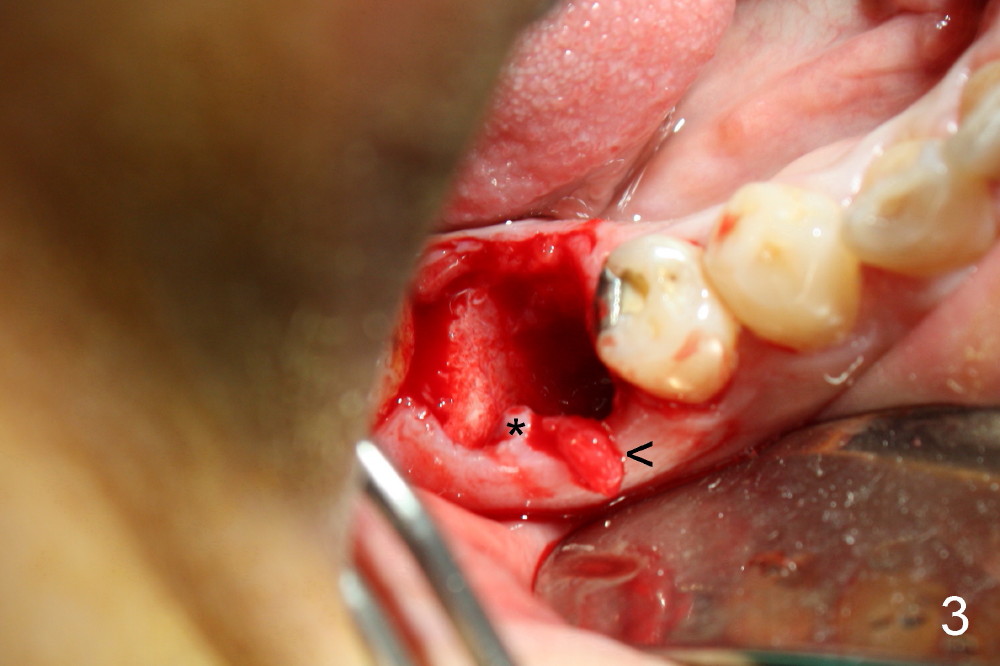

A 38-year-old lady agrees to have implant placement 7 years after loss of the crown of the lower right first molar (Fig.1,2). When the tooth is extracted, the septum is found to be low (Fig.3,4). To confirm it, a PA is taken (Fig.5). To initiate an osteotomy in the septum, it is trans-sectioned with thin osteotomes as shown in Fig.4 insert (black line). A 2 mm pilot drill is placed in the septum (Fig.6: P). The osteotomy is enlarged by 2.5-4.0 mm reamers (Fig.7,8), followed by insertion of 6x17 mm tapered tap at the depth 14 mm (Fig.9). The osteotomy is further enlarged by 4.5 and 5.0 mm reamers. A 6.0x14 mm one piece implant is placed initially. The trajectory is not ideal. A 6.0x14 mm one piece implant is placed initially. The trajectory is not ideal. The implant is removed from the osteotomy partially and reinserted with improved trajectory (Fig.11, compare to Fig.10 (red line)). Primary stability is high. There is not much bone mesiodistally so that the trajectory is easily changed in that direction. After abutment preparation, mixture of autogenous bone (harvested from reamers) and allograft is placed in the residual mesial and distal sockets (Fig.12). To contain the bone graft, an immediate provisional is placed (Fig.13 P). The occlusal plane of the provisional is significantly lower than that of the adjacent teeth to avoid micromovement of the implant. The patient is advised to eat soft food on the left side. Six days postop, the patient returns for prophy. The provisional is removed; the bone graft appears to be incorporating into the socket (Fig.14). After recementation, the provisional remains in place for 3.5 months; PA shows increased bone density in the mesial and distal sockets (Fig.15, compare to Fig.5,11). Due to insurance coverage, the patient defers fabrication of definitive restoration for at least 7 months. The immediate provisional is finally lost 8.5 months postop: the gingiva attaches to the 1-piece implant (Fig.16), while the density of the mesial socket increases (Fig.17 *) with formation of the cortex (lamina dura) coronally (v). Before the provisional (Fig.18 P) is removed for cementation of the definitive restoration, black shadow (*) is noted over the buccal gingiva. It is partially due to buccal placement (Fig.19) and partially due to buccal atrophy over a period of 10.5 months postop. How to prevent buccal placement? Positioning the first pilot drill in the septum buccolingually is a key. Eleven months post crown (Fig.20 C) cementation, the black shadow remains, but there is no tenderness. If the implant threads are immediately underneath the periosteum, there is tenderness.